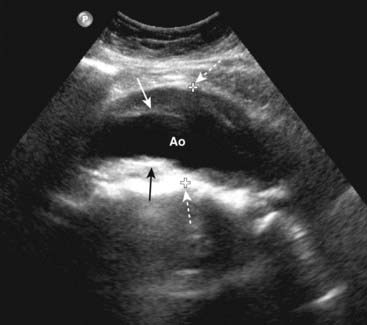

image An aneurysm is defined as a localized dilation of an artery by at least 50% over its normal size. Most aortic aneurysms occur in the abdominal aorta inferior to the origin of the renal arteries and frequently extend into one or both iliac arteries.

imageThe abdominal aorta normally measures no more than 3 cm in diameter (outer wall to outer wall).

image The size of an aneurysm is directly related to its risk of rupture. For aneurysms less than 4 cm in diameter, there is less than a 10% chance of rupture, but for aneurysms 4-5 cm in diameter, the risk of rupture increases to almost 25%.

Because it is moving, blood within the lumen of the aorta will appear anechoic; thrombus in the wall of the aneurysm will appear echogenic (Fig. 19-12).

Figure 19-12 Abdominal aortic aneurysm, sagittal view.

There is fusiform dilatation of the abdominal aorta (Ao) measuring 4.9 cm between marks (dotted white arrows). Hypoechoic thrombus is seen in the aneurysm (solid black and white arrows). Ultrasonography is the screening study of choice when an asymptomatic, pulsatile abdominal mass is palpated. For aneurysms 4-5 cm in diameter, the risk of rupture increases to almost 25%.